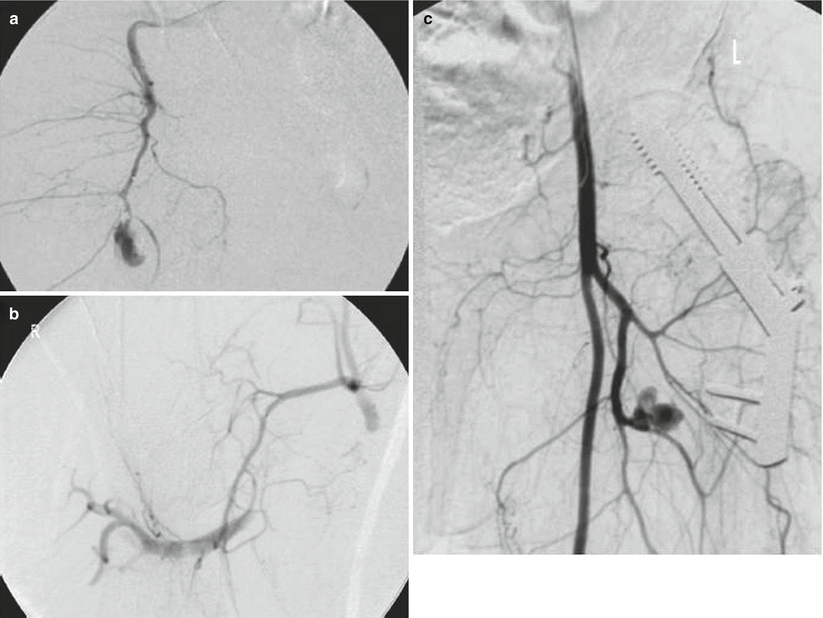

Fig. 19.2

Different imaging patterns of vessel injury presenting at angiographic evaluation. Contrast extravasation (a), arterial stump (b), and pseudoaneurysm (c)